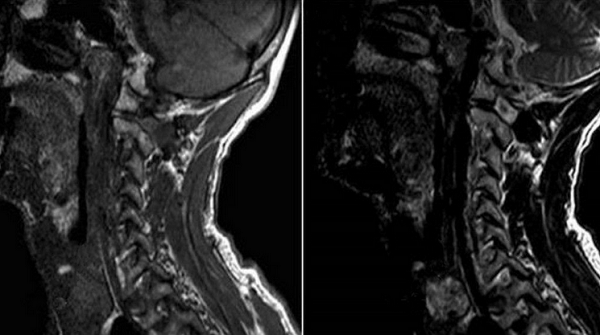

Процедура МРТ занимает от 30 минут до одного часа. Компьютер сохраняет изображения, а затем объединяет их в одно трехмерное изображение. Срезы делаются на расстоянии 1 мм, что позволяет врачу оценить состояние щитовидной железы.